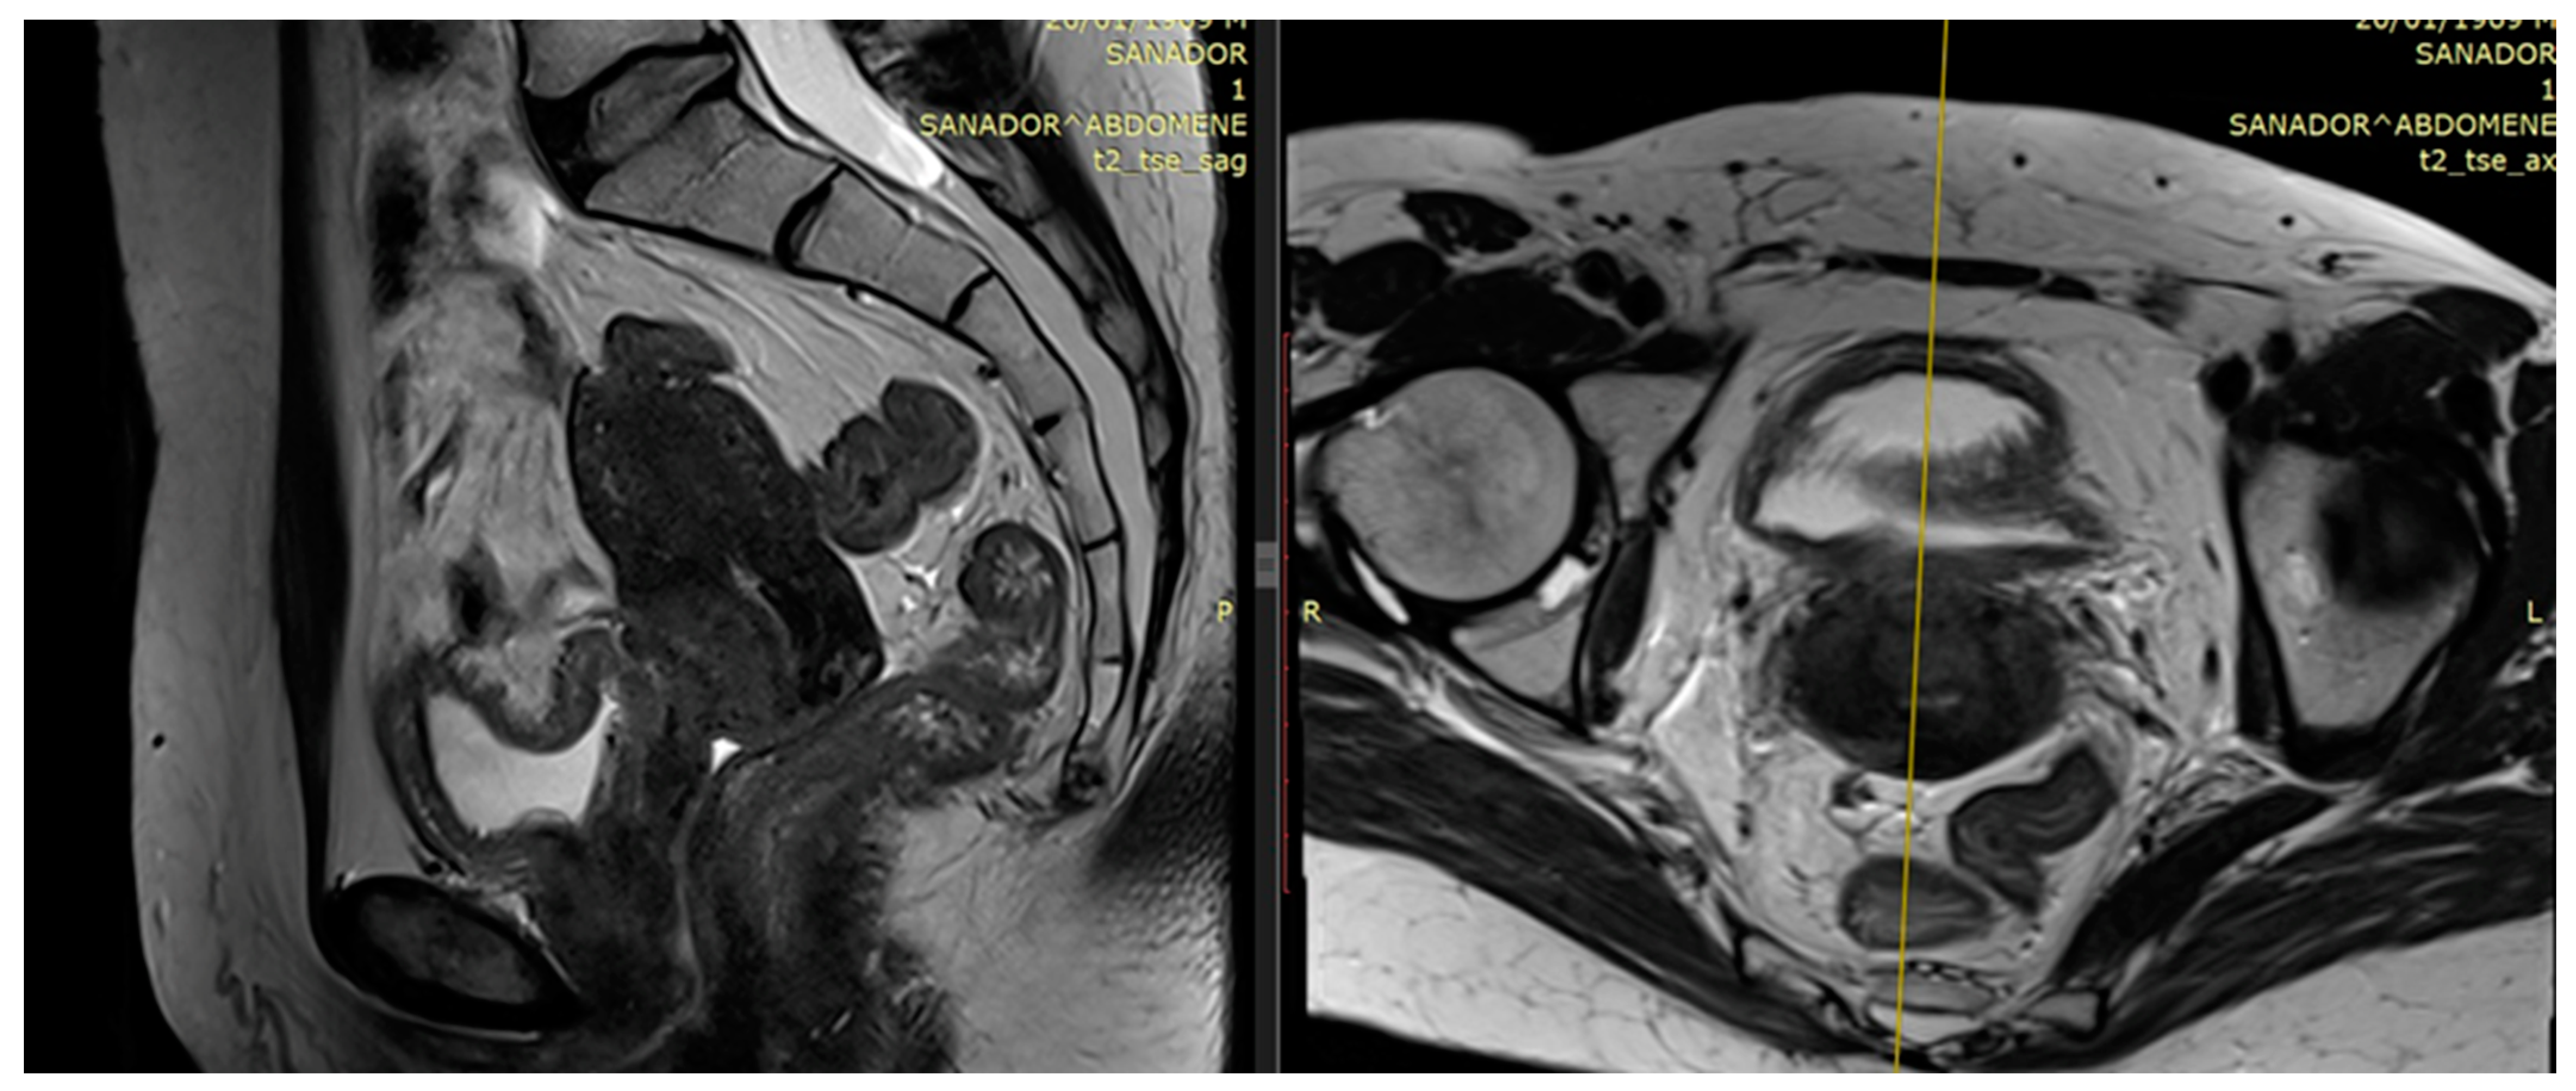

2.1. The Role of MRI